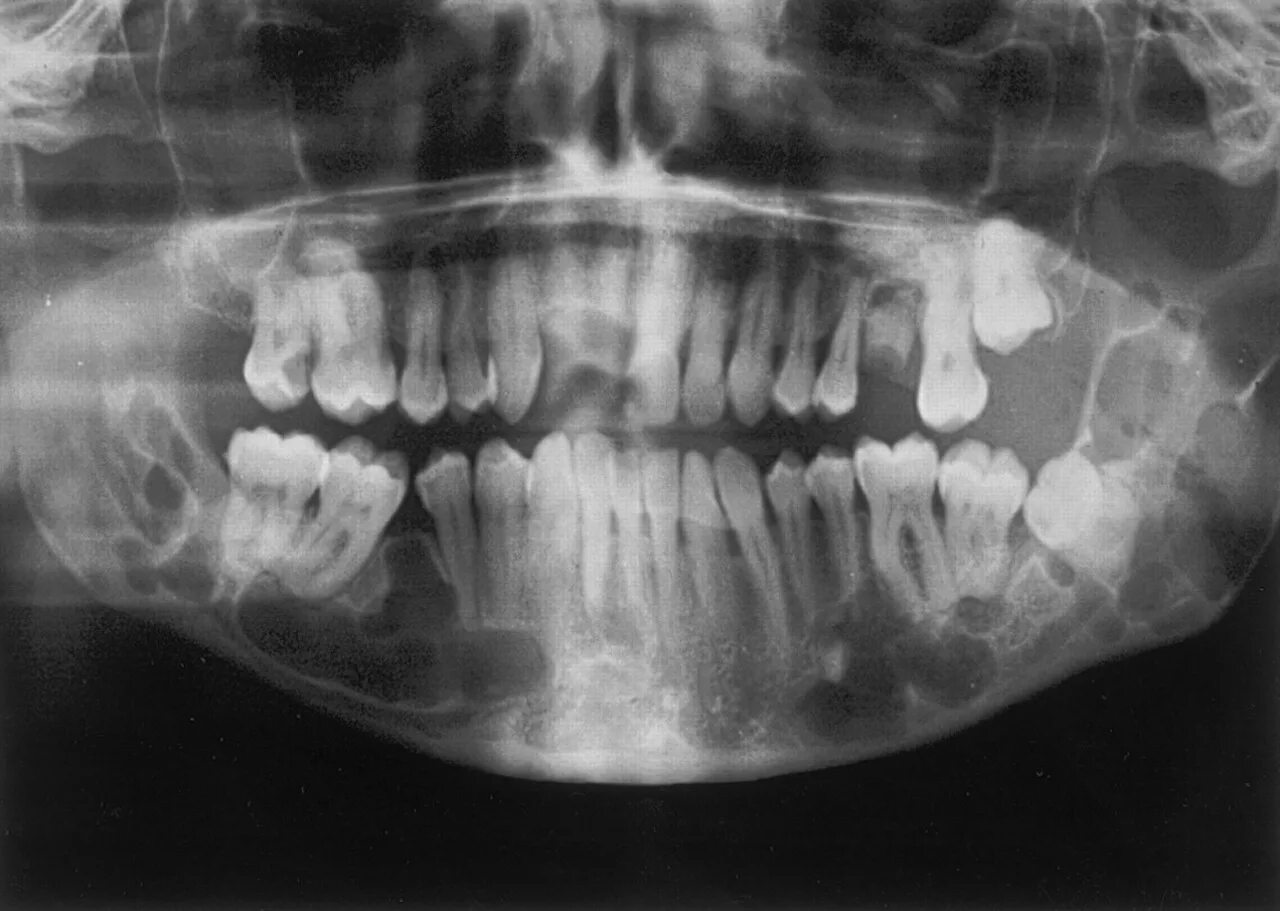

Снимок ротовой полости